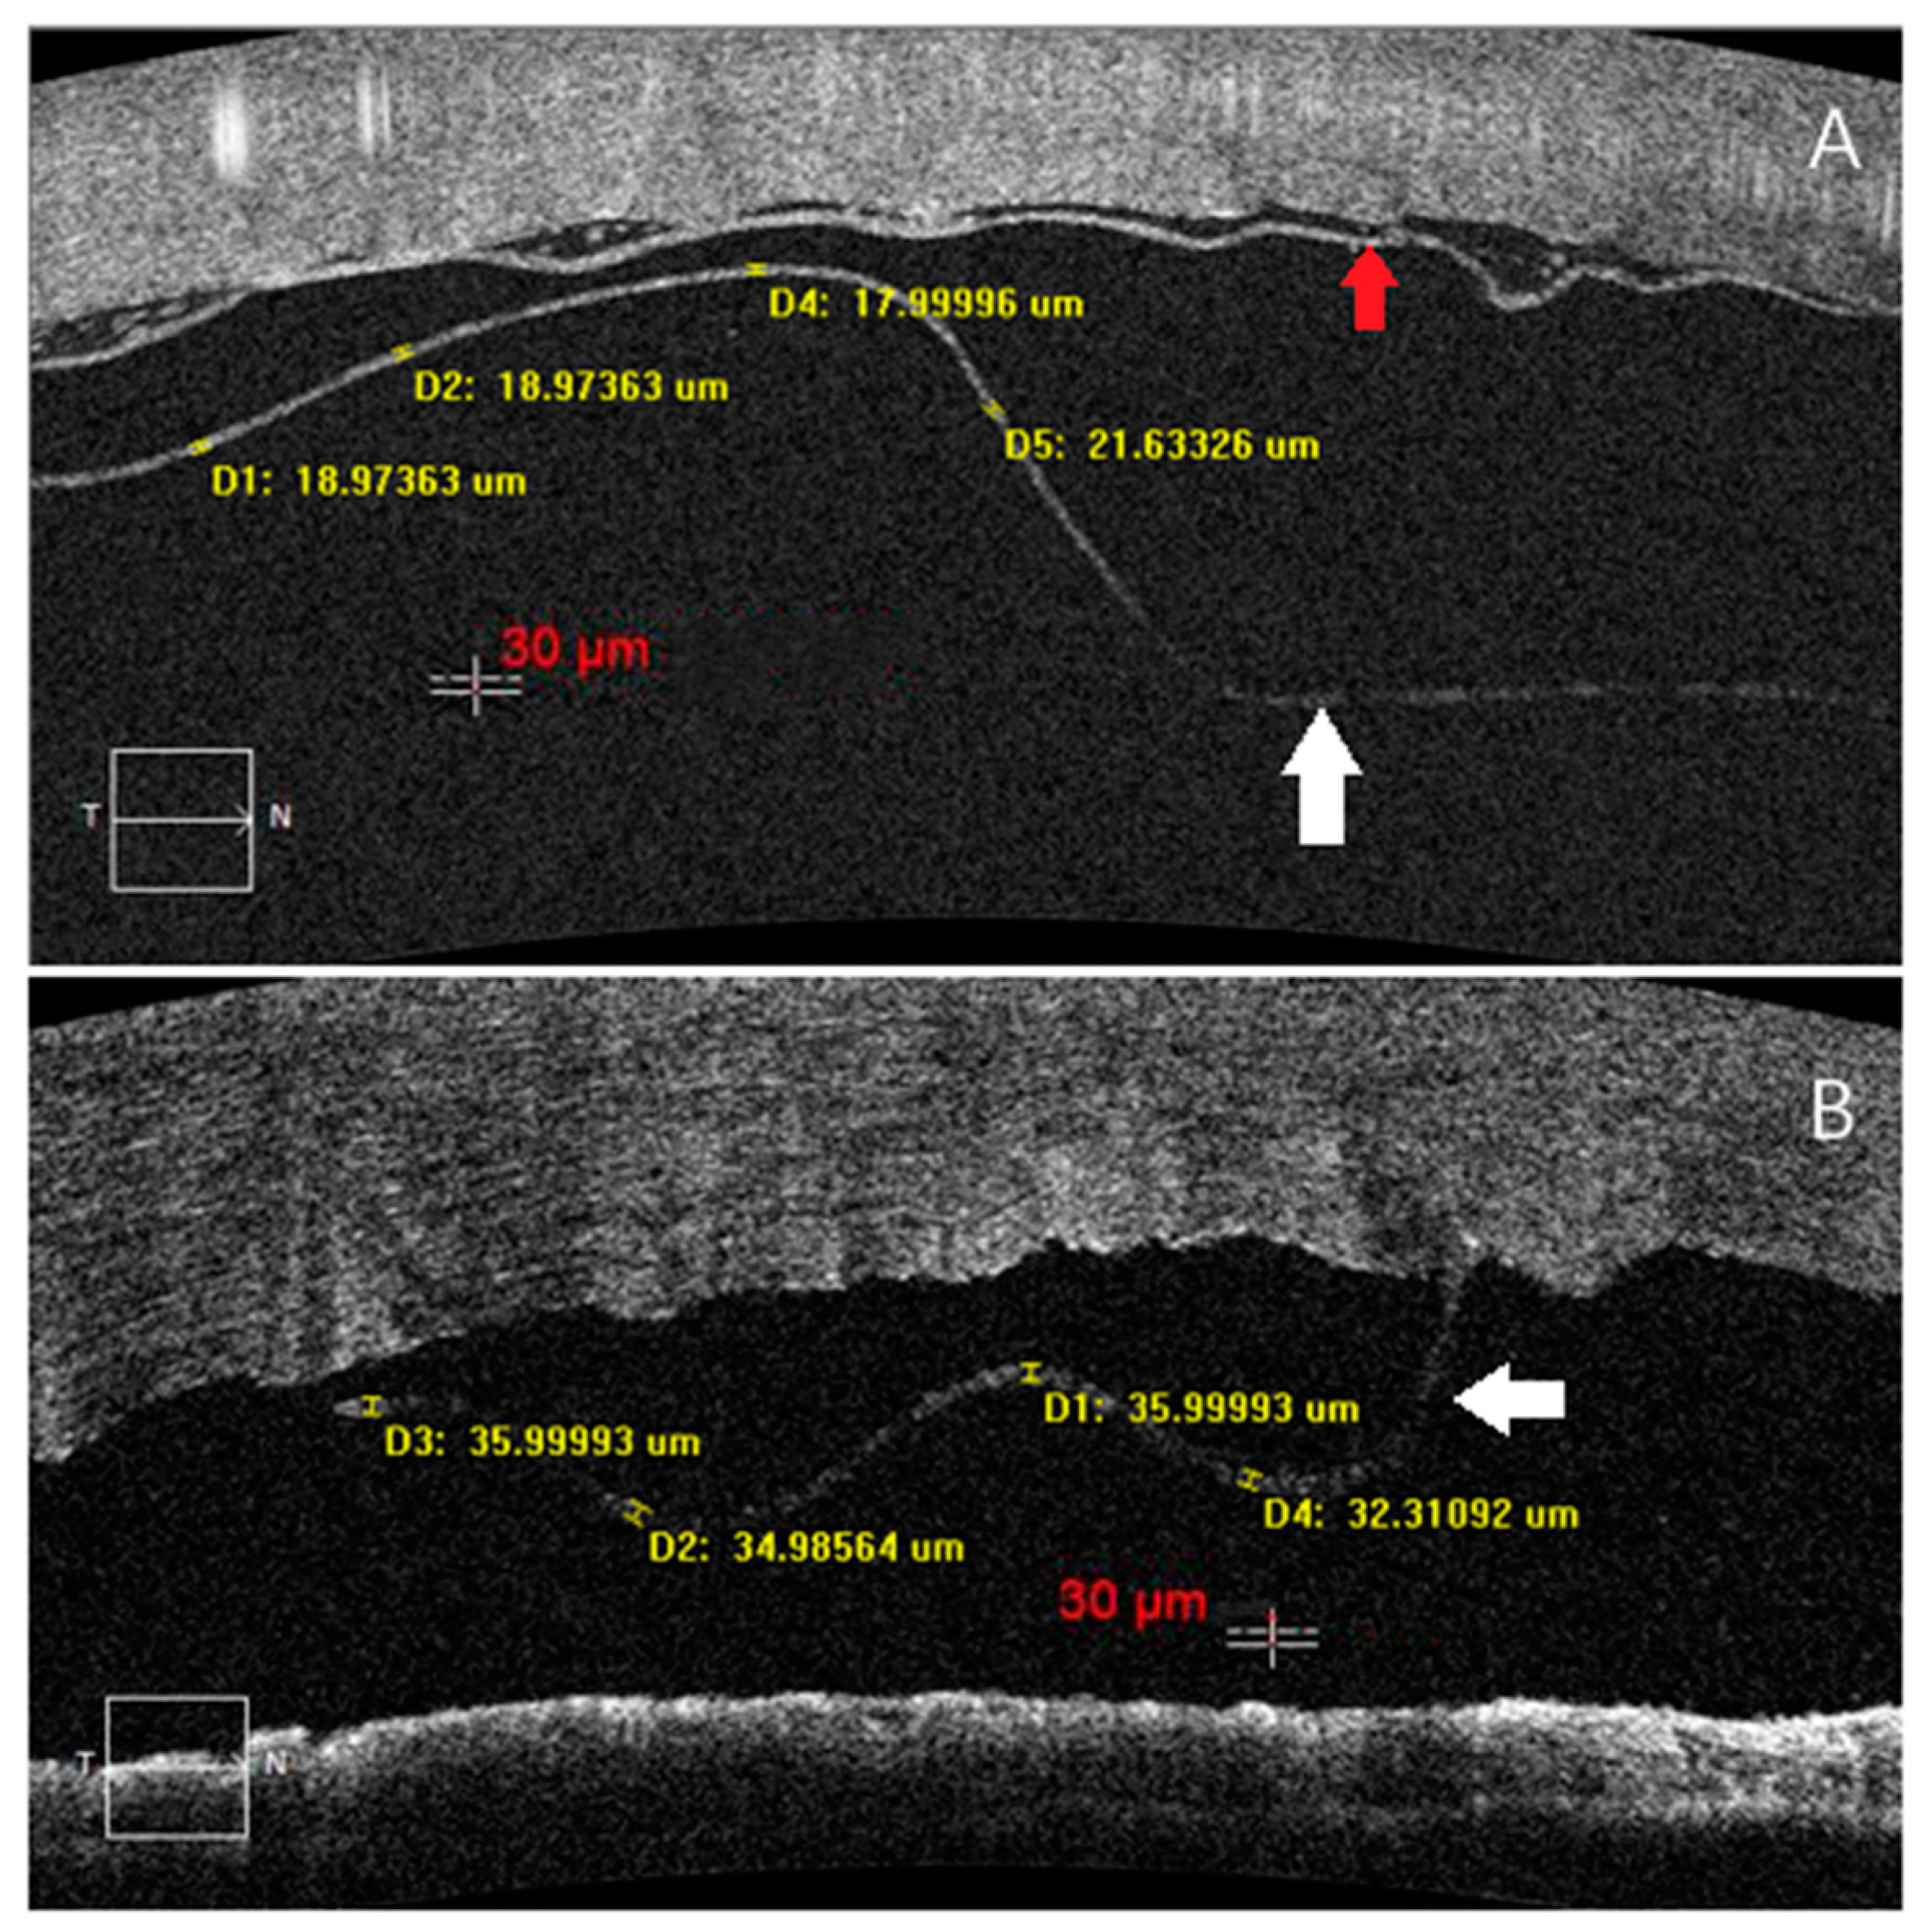

2. Subjects

3. Image Acquisition and Processing